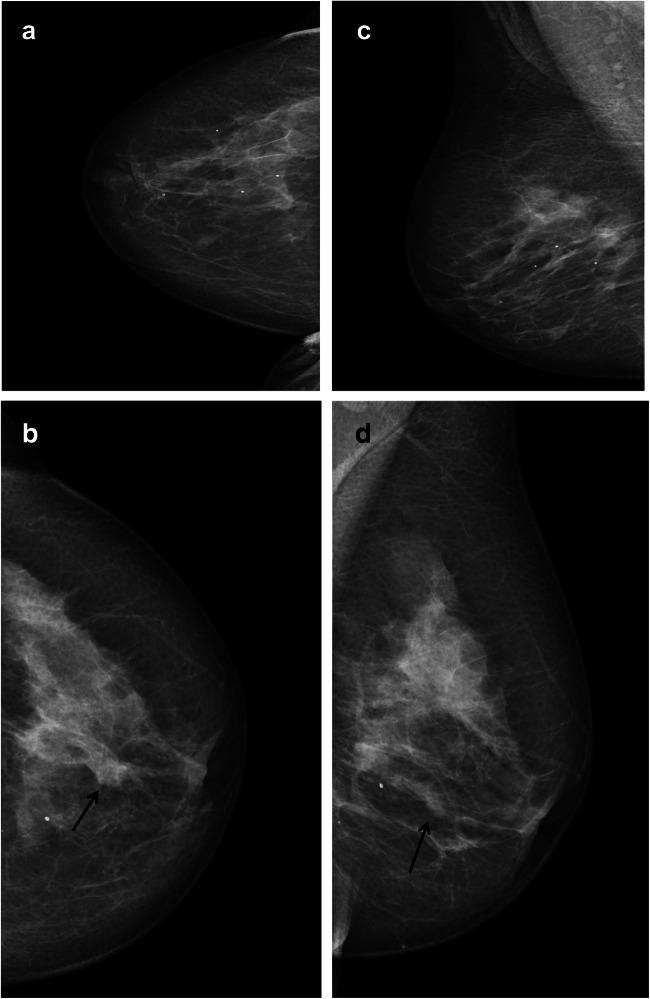

Data were extracted from the Cancer Registry of Norway for 487,118 women who participated in BreastScreen Norway, 2006-2017, with 2 years of follow-up. All mammograms were independently interpreted by two radiologists, using a score from 1 (negative) to 5 (high suspicion of cancer). A score of 2+ by one of the two radiologists was defined as discordant and 2+ by both radiologists as concordant positive. Consensus was performed on all discordant and concordant positive, with decisions of recall for further assessment or dismiss. OR was estimated with logistic regression with 95% confidence interval (CI), and histopathological tumor characteristics were analyzed for screen-detected and interval cancer.

Among screen-detected cancers, 23.0% (697/3024) had discordant scores, while 12.8% (117/911) of the interval cancers were dismissed at index screening. Adjusted OR was 2.4 (95% CI: 1.9-2.9) for interval cancer and 2.8 (95% CI: 2.5-3.2) for subsequent screen-detected cancer for women dismissed at consensus compared to women with concordant negative scores. We found 3.4% (4/117) of the interval cancers diagnosed after being dismissed to be DCIS, compared to 20.3% (12/59) of those with false-positive result after index screening.

Twenty-three percent of the screen-detected cancers was scored negative by one of the two radiologists. A higher odds of interval and subsequent screen-detected cancer was observed among women dismissed at consensus compared to concordant negative scores. Our findings indicate a benefit of personalized follow-up.

• In this study of 487,118 women participating in a screening program using independent double reading with consensus, 23% screen-detected cancers were detected by only one of the two radiologists. • The adjusted odds ratio for interval cancer was 2.4 (95% confidence interval: 1.9, 2.9) for cases dismissed at consensus using concordant negative interpretations as the reference. • Interval cancers diagnosed after being dismissed at consensus or after concordant negative scores had clinically less favorable prognostic tumor characteristics compared to those diagnosed after false-positive results.